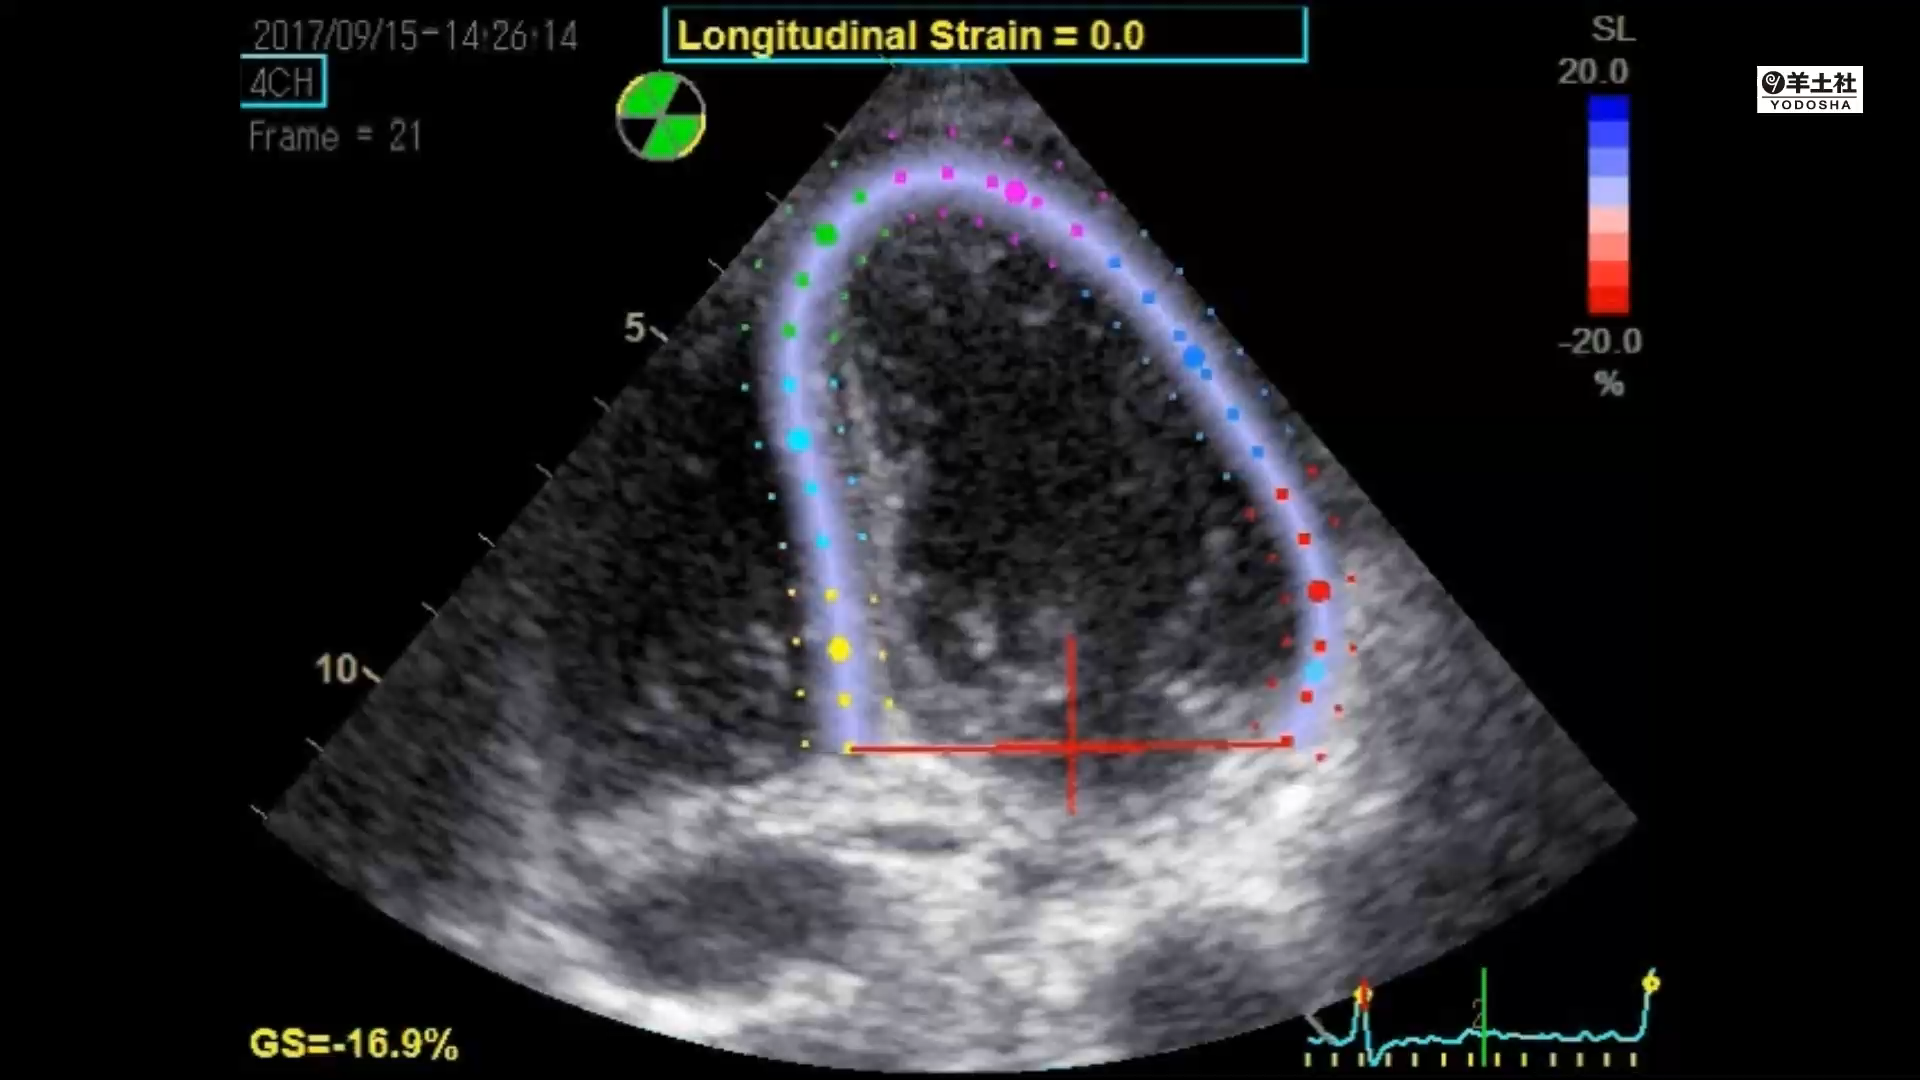

2Dスペックルトラッキング法による長軸方向ストレイン

1 左室駆出率/2 心拍出量の求め方/3 ドプラによる左室dP/dtの推定/4 2Dスペックルトラッキング法による長軸方向ストレイン